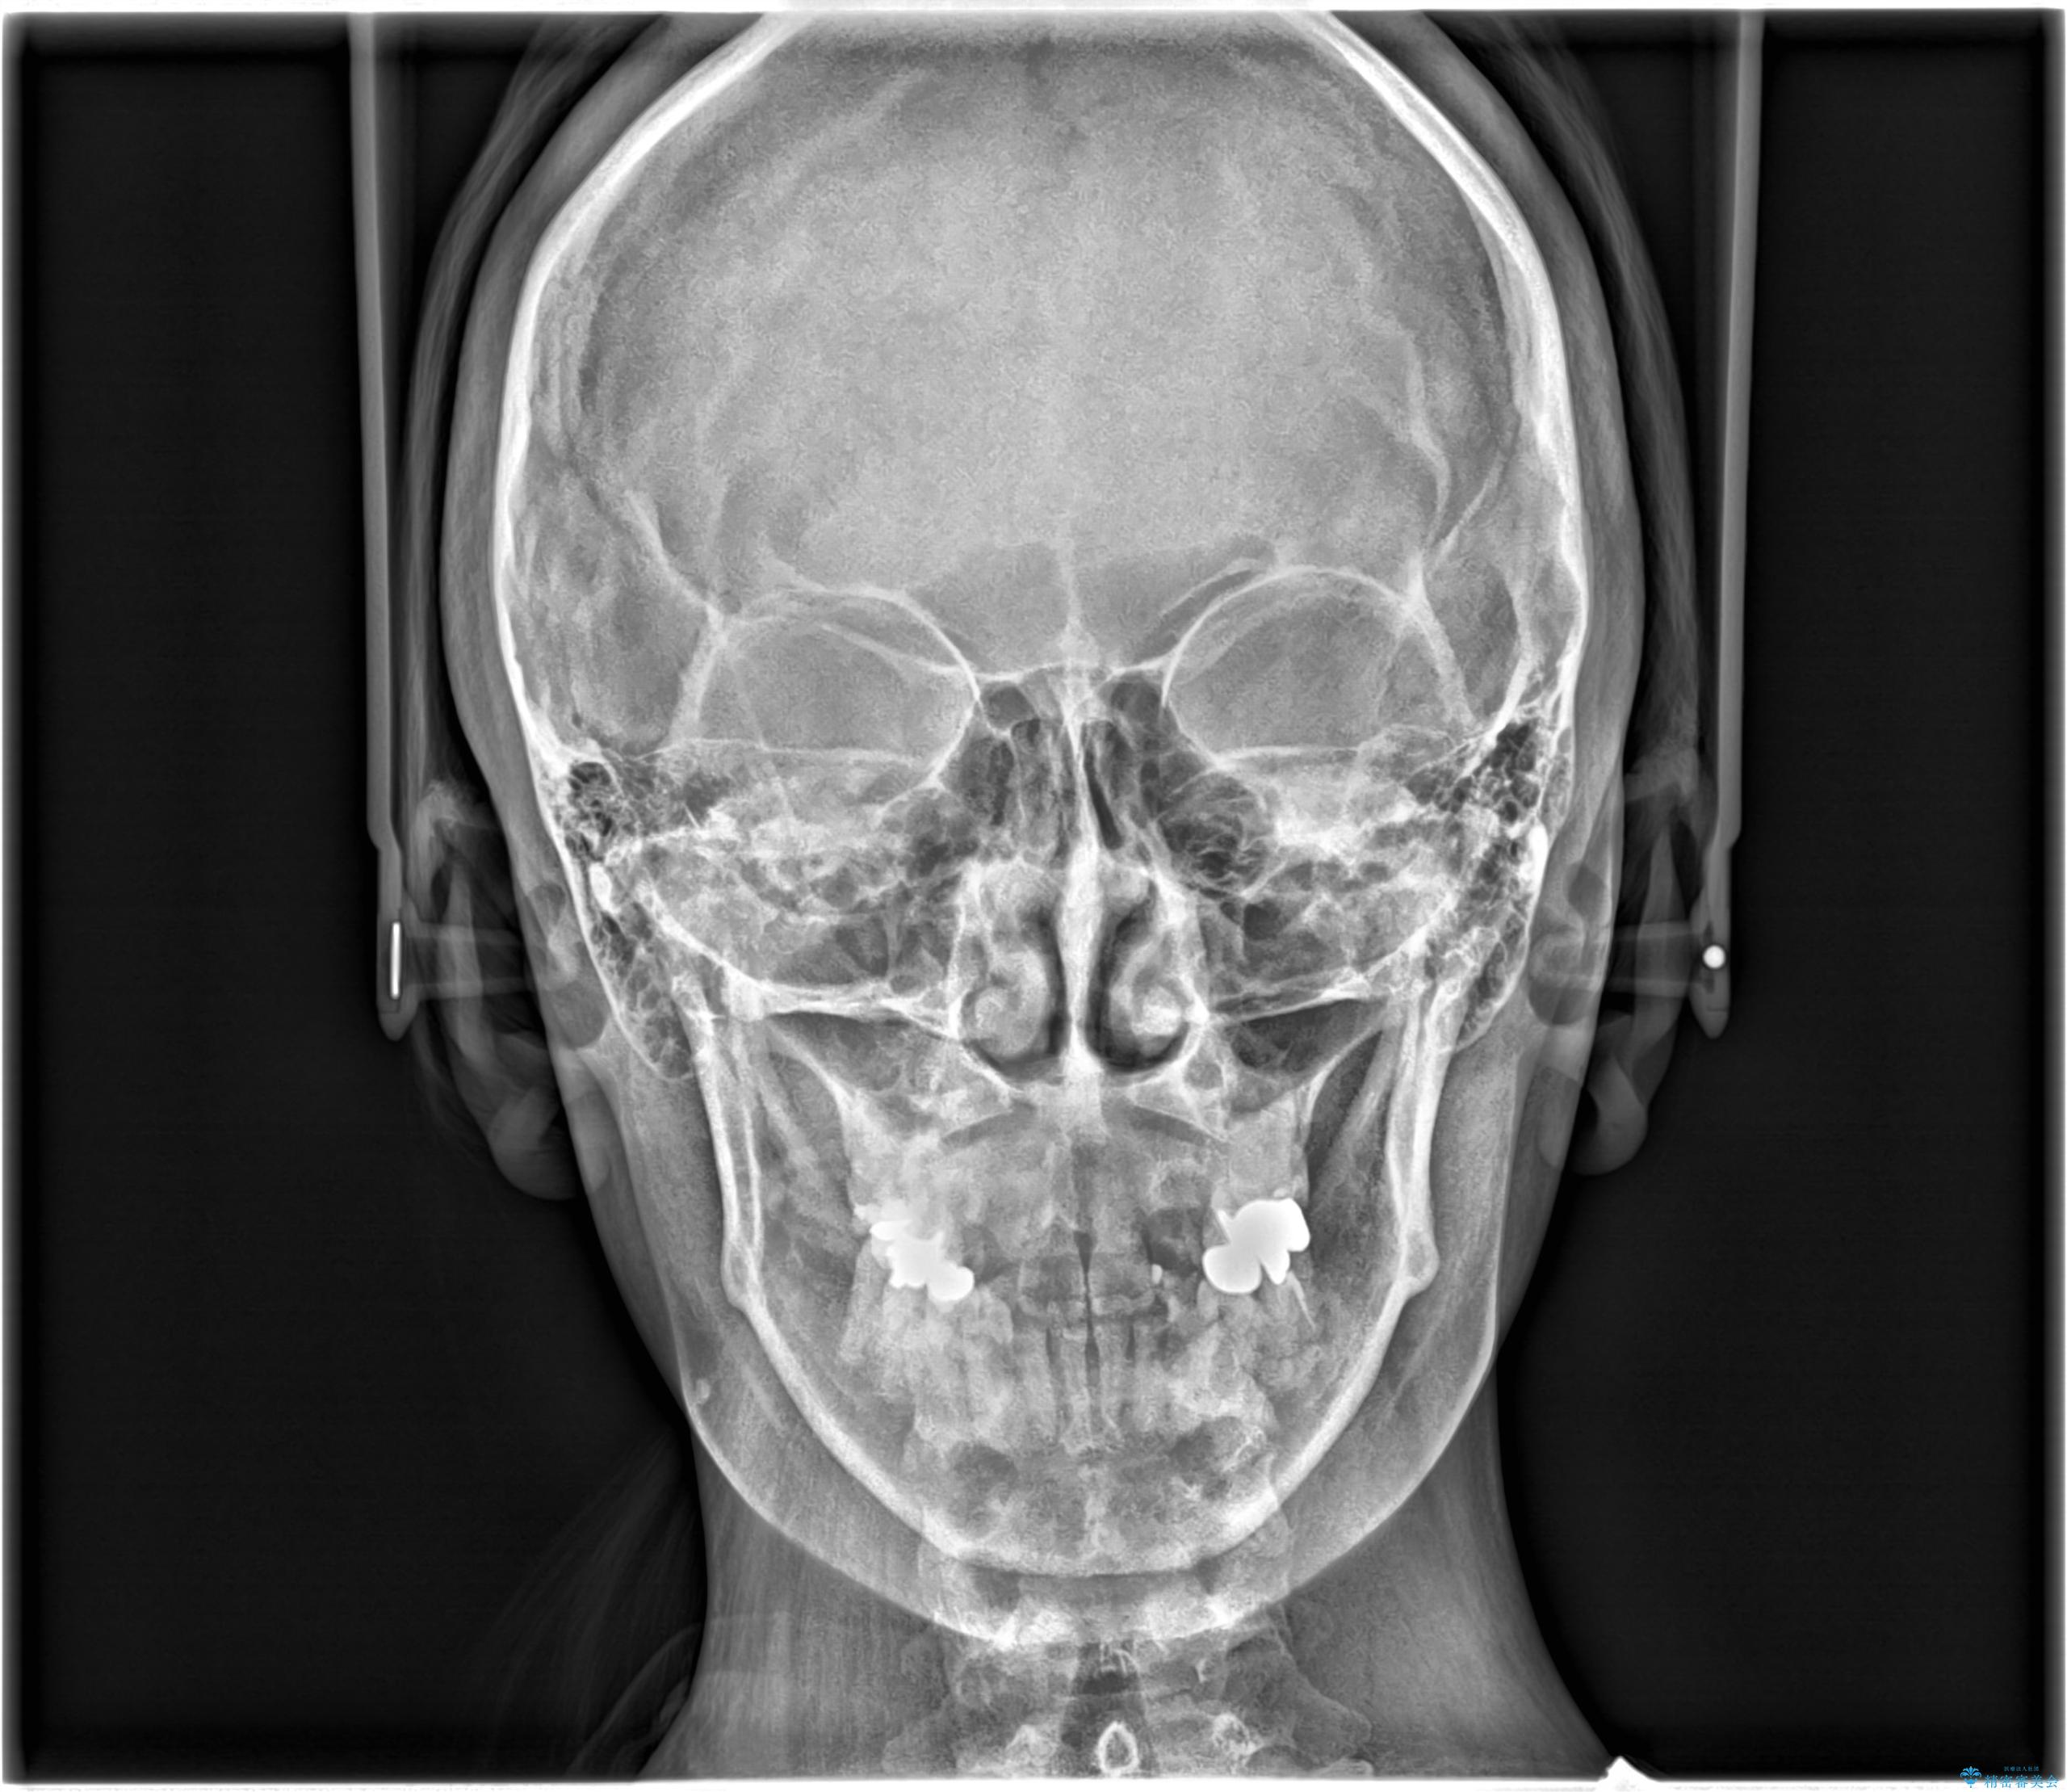

- 開咬と歯のデコボコ(叢生)、八重歯を主訴にご来院された患者様です。

矯正の精密検査の結果、上顎左右4番および下顎左右5番の計4本を抜歯し、ワイヤー矯正(クリア装置)にて治療を行いました。